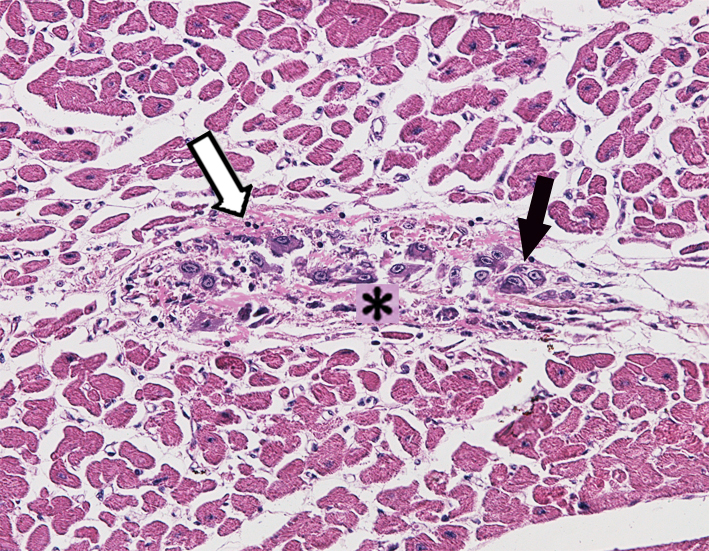

6.Myocardial infarction